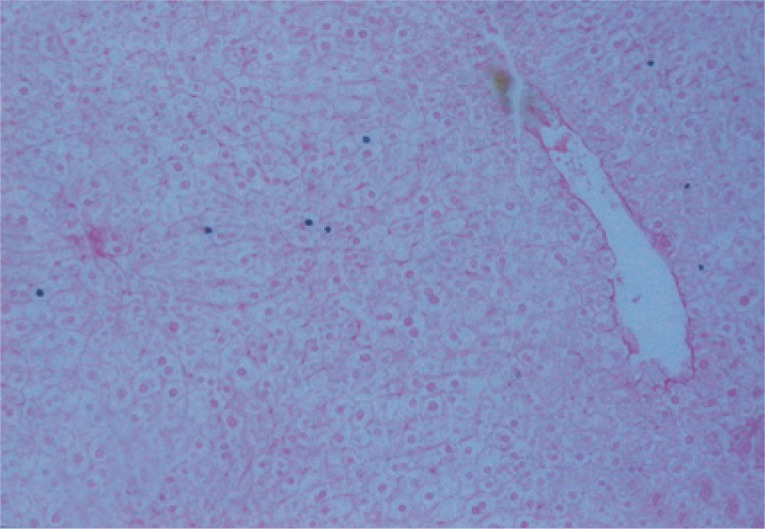

Liver specimens were fixed in 10% formalin, processed to paraffin blocks, and sectioned at 4 µm thickness. Sections were stained with hematoxylin and eosin (H&E) to study the hepatic morphological changes and hepatic schistosomal fibrosis [19].

Liver sections were examined by a light microscope regarding the exerted hepatic schistosomal infection and portal fibrosis through the periods of the experiment [20]. This study focused on tracing the homing of the transplanted BMSCs and their differentiation into newly formed hepatocytes [19], applying immunohistochemistry techniques using monoclonal anti-mouse anti-OV-6 antibodies for detection of newly formed hepatocytes.

The mean granuloma count in the treated groups with BMSCs and BMSCs-HGF revealed a marked reduction accompanied by an obvious reduction in the mean granuloma number and diameter (Table 1; Figs. 2, 3).